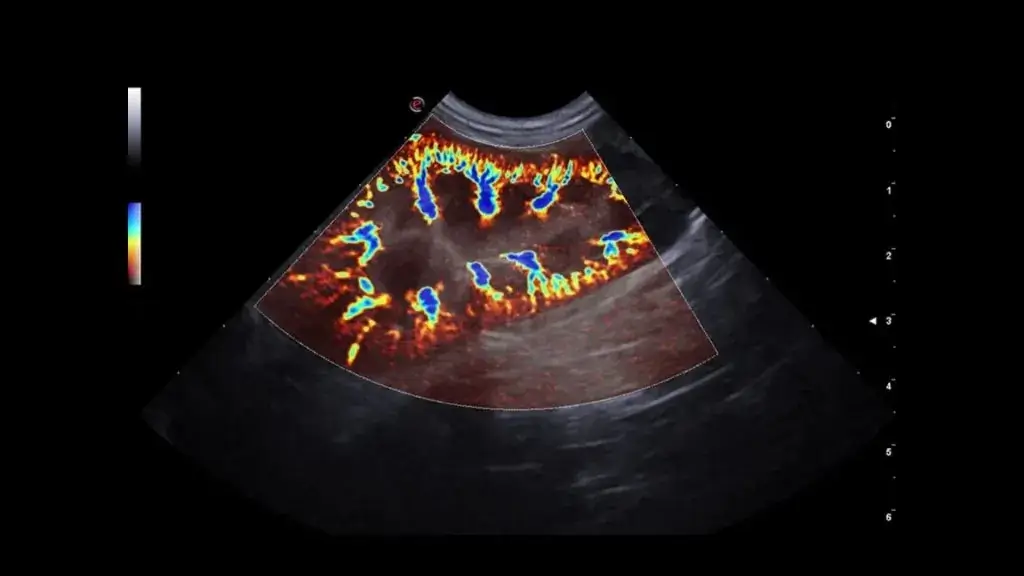

• Gerekli görülen durumlarda Doppler USG ile kan akımı analizi yapılabilir.

Gerekli durumlarda Doppler ile direnç indeksi gibi parametreler incelenebilir.

Karaciğer parankimi, portal/hepatik damarlar, safra kesesi ve biliyer sistem değerlendirilir.

Gerekli durumlarda Doppler ile vasküler yapıların analizi yapılabilir; portosistemik şant şüphesinde yönlendirici olabilir.

Teknik Altyapımız

Merkezimizde, veteriner kullanımı için üst düzey teknik özelliklere sahip renkli Doppler ultrasonografi sistemi ile hizmet verilmektedir. Cihaz altyapımız; gerçek zamanlı görüntüleme, Doppler kan akımı analizi ve yüksek çözünürlüklü değerlendirme imkânı sunarak birçok patolojinin tanısında hekimlerimize güçlü bir klinik destek sağlar.